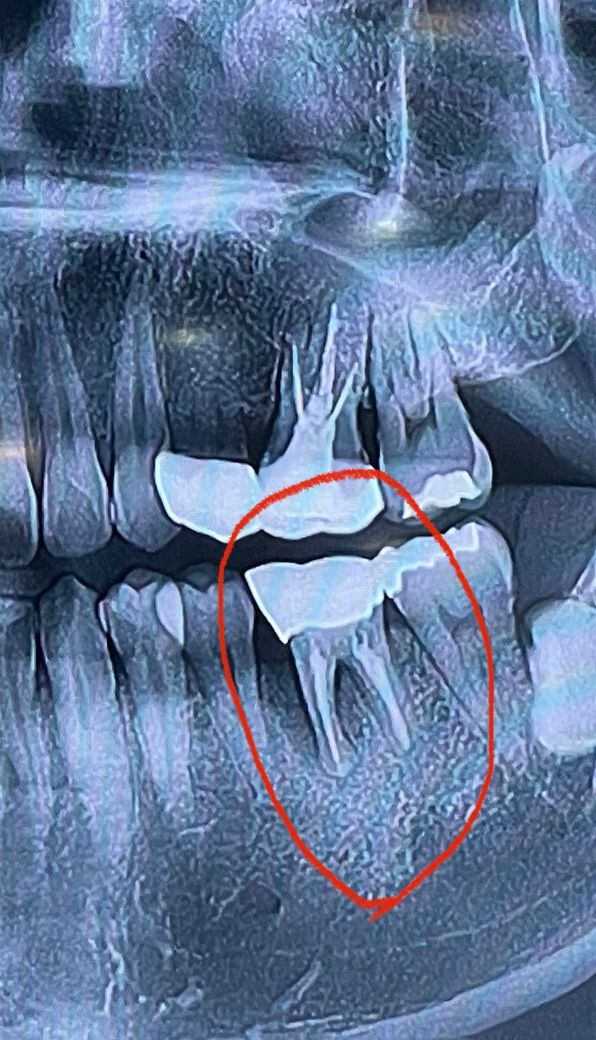

어금니 뿌리가 2가닥인데 앞쪽 가닥의 잇몸뼈 파괴가 심하고 염증이 보입니다. 이런 정도면 치아를 살리기 힘든 상황입니다.

사진상으로 보면 잇몸뼈가 많이 녹아잇는거 같습니다. 발치를 해야될 가능성이 높아 보입니다.

직접 검사를 해보신 선생님들이 더 정확한 진단을 내리셨겠지만 사진상으로는 발치가 필요한 치아입니다